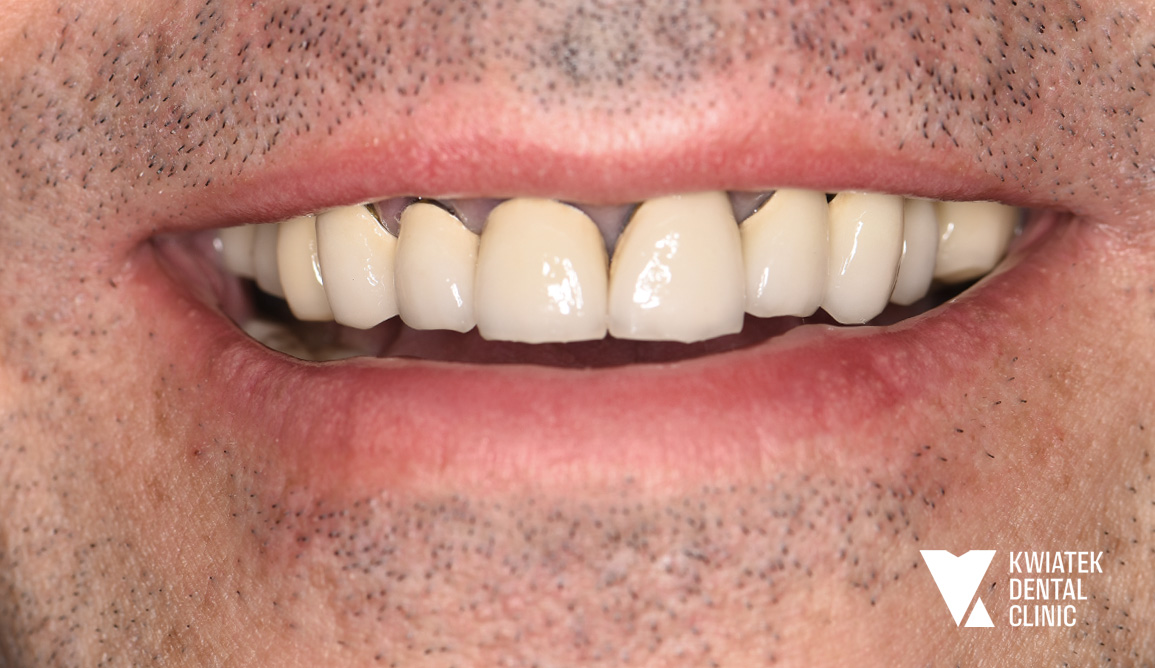

Pełna rekonstrukcja zwarcia i estetyki - historia wymagającej metamorfozy

Pacjent zgłosił się do kliniki z zaawansowanymi problemami stomatologicznymi: licznymi ubytkami próchnicowymi, brakami zębowymi, starciem zębów oraz zaburzeniami zwarcia. Leczenie obejmowało kompleksową diagnostykę, leczenie zachowawcze i endodontyczne, zabiegi chirurgiczne, implantację oraz wieloetapową odbudowę protetyczną. Efektem terapii jest perfekcyjnie zbalansowany zgryz, najwyższy komfort funkcjonowania oraz naturalnie piękny uśmiech, który podkreśla indywidualny charakter pacjenta i pozwala mu w pełni cieszyć się nim każdego dnia.